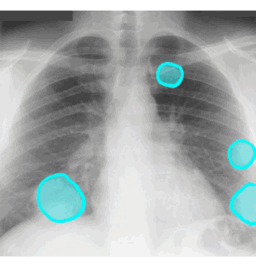

B

SHAPE - round

MARGIN - smooth

SIZE - from 1 to 4 cm

DENSITY - soft tissue

NOTE: any round lung opacity that is more than 3 cm in diameter must be called a 'MASS'